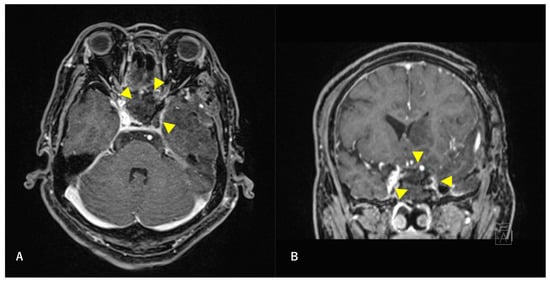

Figure 2. Preoperative T2-weighted magnetic resonance image (MRI) findings. Axial section (A) and coronal (B) images are shown. A high-intensity mass is observed in the left sphenoid sinus. The ICA is surrounded by a mass. Arrowheads indicate tumors.

A 60-year-old man without any symptoms presented to the otorhinolaryngology department with a suspected neoplastic lesion in the left sphenoid sinus, detected on magnetic resonance imaging performed during a physical examination. Imaging modalities showed that the tumor extended from the left sphenoid sinus to the area surrounding the ICA, with associated bone destruction, raising a suspicion of malignancy (Figure 1 and Figure 2). Neither regional lymph node nor distant metastases were observed. An otorhinolaryngologist performed a transnasal biopsy of the tumor under general anesthesia to determine the course of treatment. Immunohistochemical staining was positive for cluster of differentiation (CD) 56, synaptophysin, and chromogranin A. In contrast, cytokeratin AE1/AE3 staining was negative (Figure 3). Notably, there were few S-100 protein-positive cells, which are suggestive of the sustentacular cells typical of ONB. Because the diagnosis was difficult, the pathologists referred the specimens to a more specialized laboratory for additional testing. Further immunohistochemical tests were negative for both Nirenberg and Kim homeobox (NKX) 2.2 and CD99; therefore, the patient was diagnosed with olfactory neuroblastoma with Hymas pathological grade I and Kadish stage C.